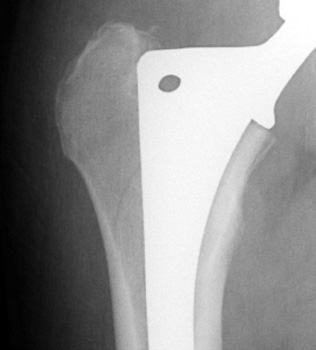

Intraoperative fracture of the proximal femur.

Intraoperative fracture of the femur at the tip of the femoral stem.